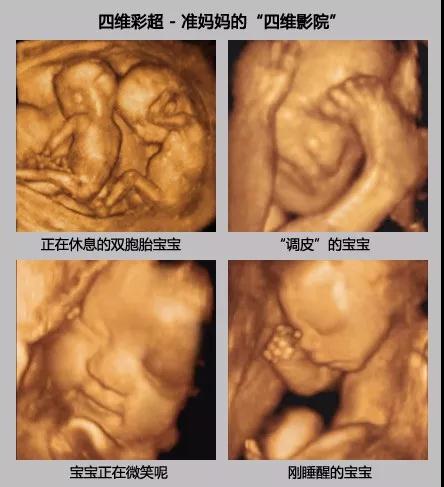

不管是无论一胎还是二胎,许多宝妈们对于四维彩超,还是存在很多的疑问,我挑了几个大家比较关心的问题,对大家进行一下小科普。